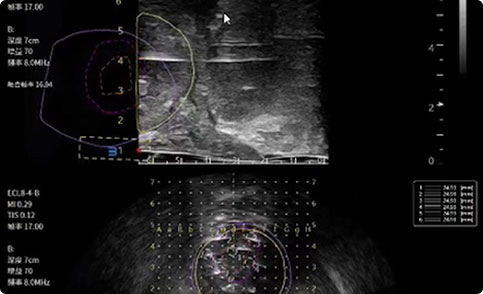

前列腺增生

研究结果:手术组尿流率增加显著优于药物组,且手术治疗过程严重不良反应发生率0%,且手术时间平均约15min,创伤较小,患者一般当天可下床。